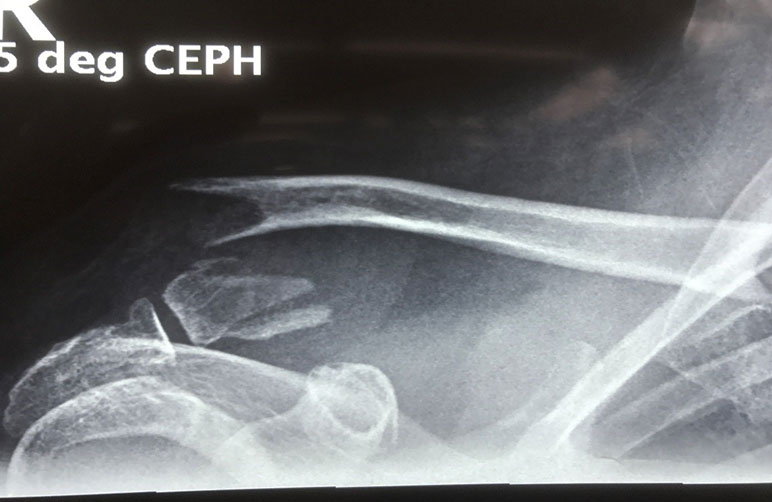

What do clavicle fractures look like on X-ray?

Below are examples of typical fractures that benefit from surgery.

A 15 year old female fell from her pushbike causing a displaced left mid-shaft clavicular fracture. Seen 5 days later, plate & screws inserted 2 days later.

Image

DIsplaced fracture before surgery